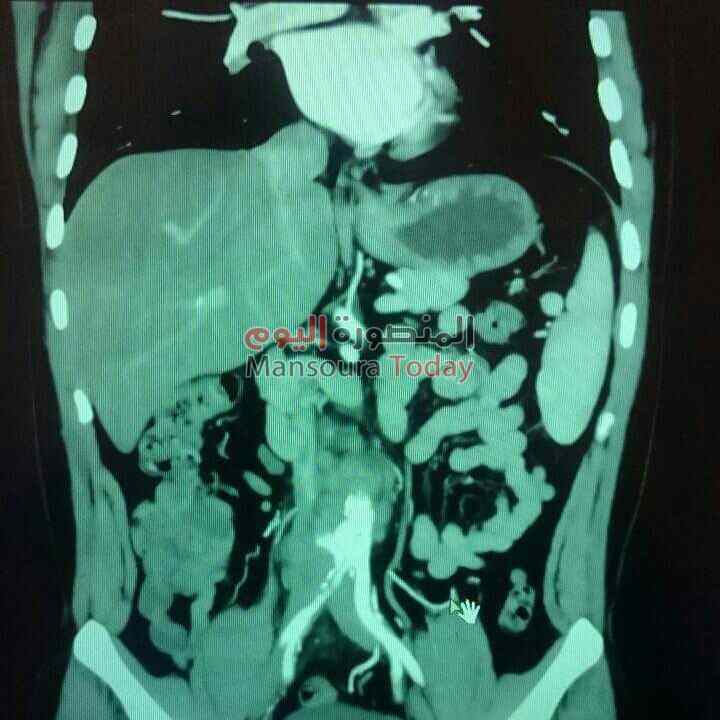

تمكن فريق جراحى بقسم فريق جراحه الأوعية الدمويه برئاسة الدكتور مسعد سليمان ، بإجراء أول حاله تمدد بشريان الأورطي باستخدام القسطرة التداخلية بجامعة المنصورة .

يضم الفريق الدكتور تامر عبد الحي ، الدكتور محمد فرج ، الدكتور محمد شكري ، الدكتور أحمد مسعد ، الدكتور نشأت محمد ، وأشار الدكتور مسعد مريض تعافي بعد القسطره وتم الاطمئنان عليه وينتظر خروجه في خلال ٤٨ ساعة ، مشيرا أن حالة التمدد بشريان الأورطى بسبب ضعف جزء من جدار هذا الشريان بالبطن مما يؤدي إلى التمدد وخطورة الانفجار بسبب ضغط الدم المتواجد بداخله ، ومعظم تمدد الأوعية الدموية يحدث في ذلك الجزء من الشريان الأورطي الذي يمر في البطن ويسمى تمدد الشريان الأورطي البطني ، إذا كان التمدد كبيراً جدا يمكن أن يسبب آلاماً مبرحة وتورماً في البطن يكبر تدريجياً وإذا انفجر فقد يسبب نزيفاً داخلياً شديداً غالبا ما يكون مميتاً إلا عندما يتم إنقاذ الموقف بعملية جراحية سريعة.